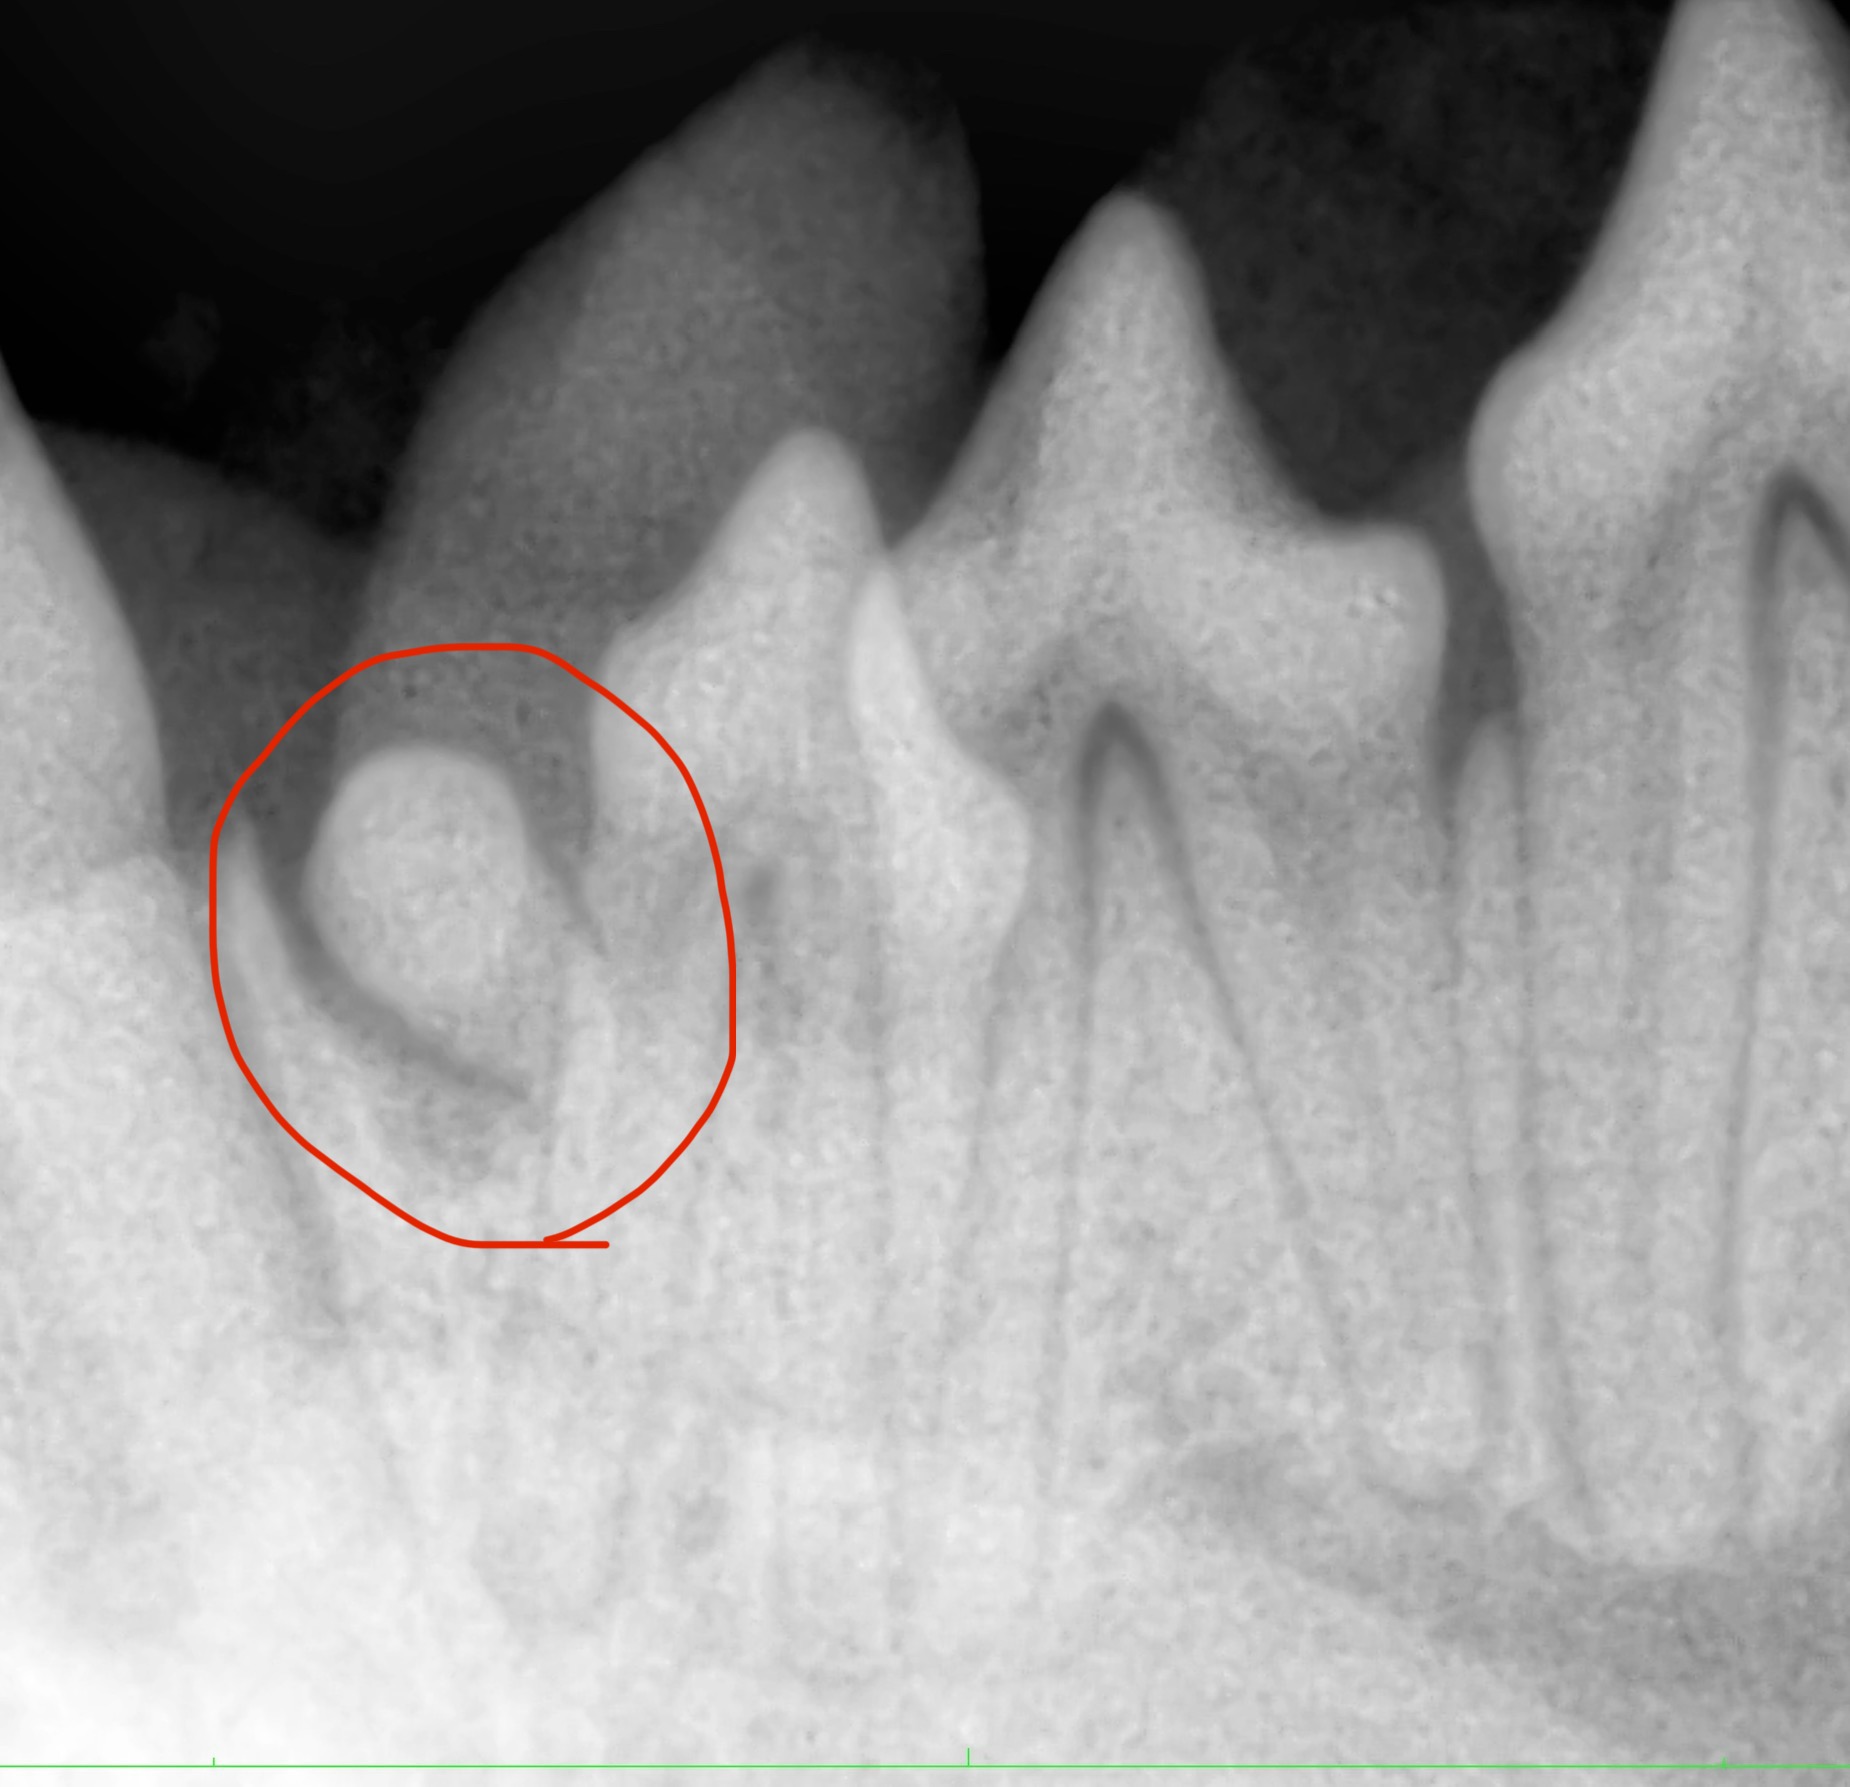

【歯科・外科症例】歯が足りない?「埋伏歯」と短頭種の呼吸ケア

こんにちは! 世田谷区等々力のけいこくの森動物病院です🌳 一見「歯が足りないだけ」に見える状態が、実は「埋伏歯」という放っておくと危険なサインかもしれません。 今回は1歳6ヵ月で埋伏歯の抜歯と短…